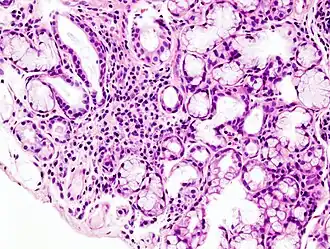

![]() Imagen histopatológica de infiltración en la glándula salivar menor asociada con la enfermedad de Sjögren. Biopsia labial. H & E stain. | ||